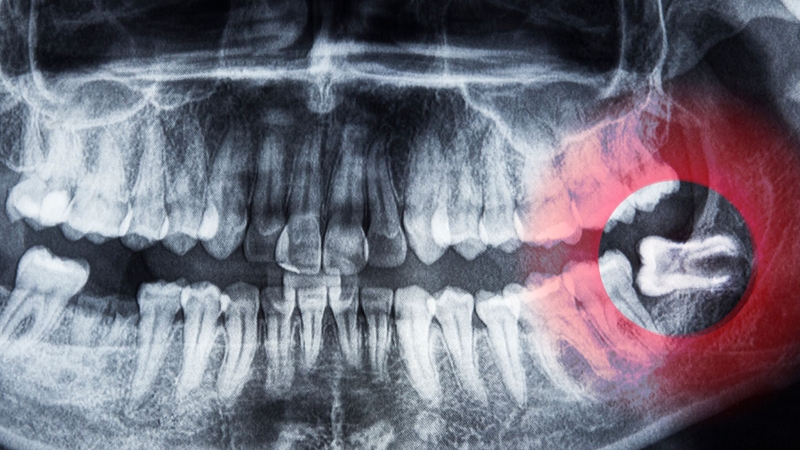

Răng khôn là chiếc răng hàm cuối cùng thường mọc trong độ tuổi 17 đến 25. Do vị trí nằm sâu bên trong cung hàm, quá trình mọc răng khôn thường không dễ dàng. Nhiều người cảm thấy đau, nướu sưng đỏ, thậm chí xuất hiện sốt.

Thực tế, mọc răng khôn không phải lúc nào cũng gây sốt. Một số trường hợp mọc răng bình thường chỉ có cảm giác căng tức và khó chịu nhẹ. Tuy nhiên, nếu răng mọc lệch hoặc chỉ trồi lên một phần, phần lợi che phủ dễ bị viêm nhiễm. Khi đó, sốt có thể xuất hiện như một phản ứng của cơ thể trước tình trạng viêm.

Mọc răng khôn bình thường ít khi gây sốt. Sốt thường xảy ra khi vùng lợi quanh răng khôn bị viêm hoặc nhiễm trùng. Đây là tình trạng gọi là viêm lợi trùm. Khi lợi bị sưng, vi khuẩn dễ xâm nhập vào khe hở giữa lợi và răng. Lúc này cơ thể phản ứng bằng cách tăng thân nhiệt để chống lại vi khuẩn.